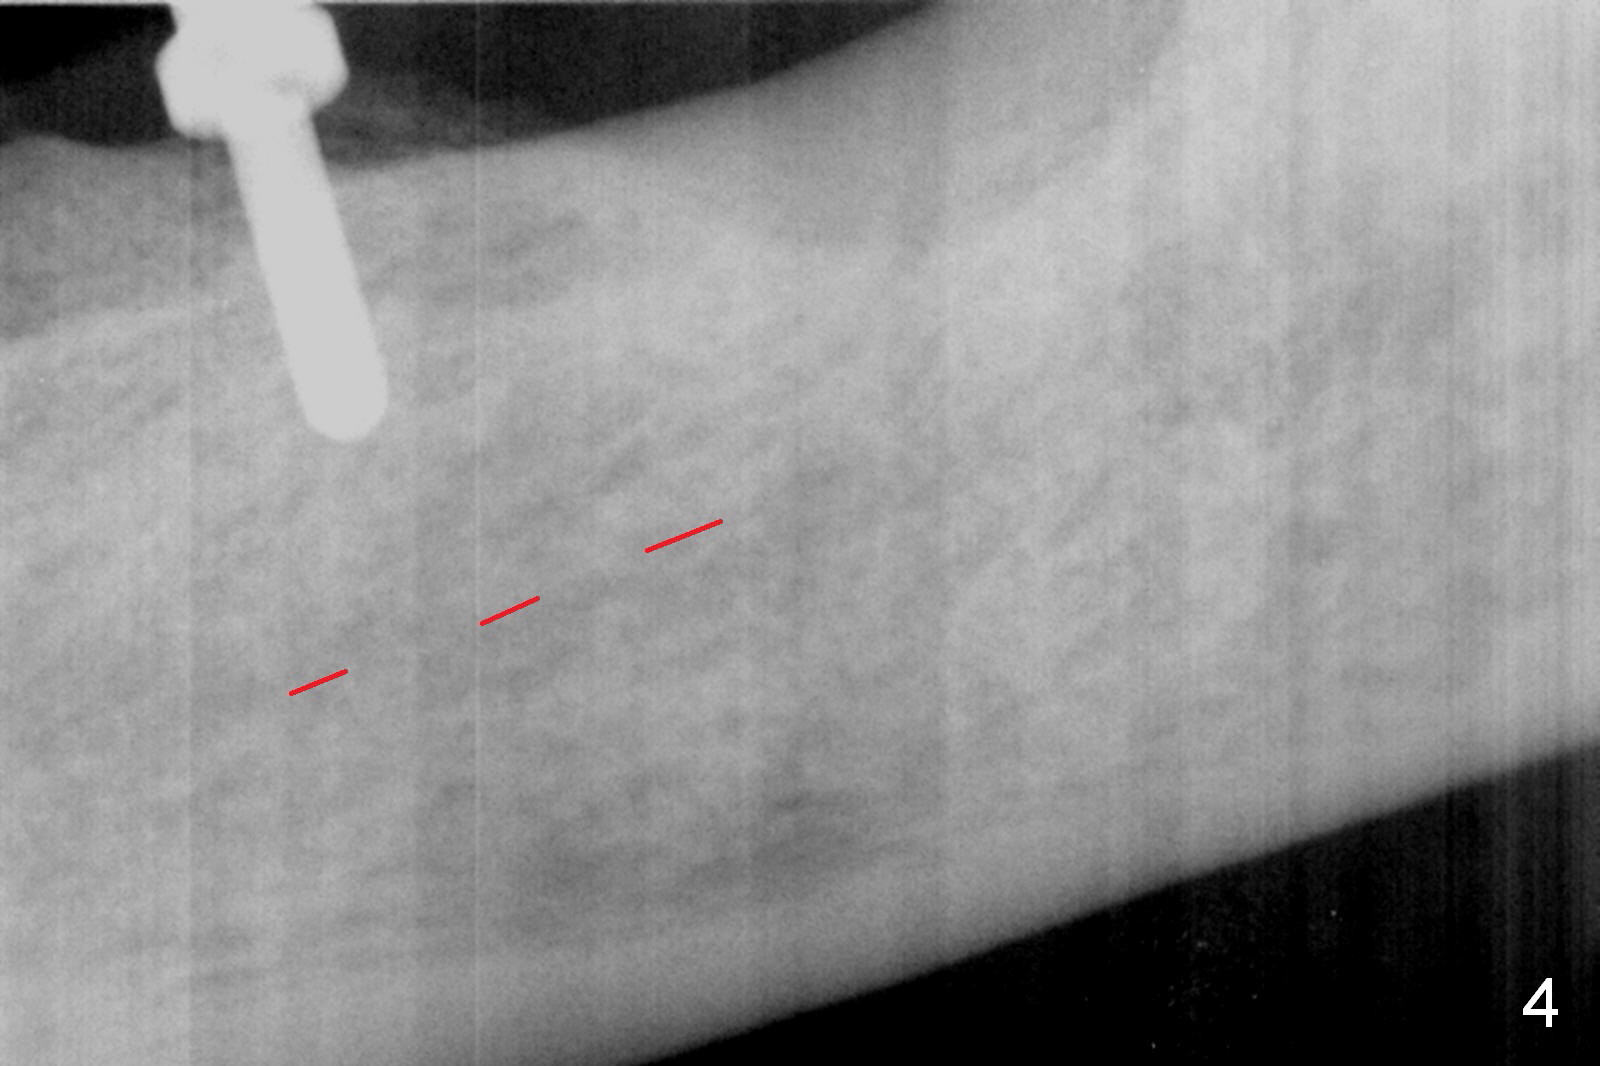

Except the tooth #30, the patient is completely edentulous (Fig.1,2). His chief complaint is "food gets into the missing tooth area". Due to short guide pin (Fig.3) and parallel pin (Fig.4), it is difficult to calculate precisely at the site of #19 the distance to the superior border of the Inferior Alveolar Canal (Fig.4 red dashed line). The clearance appears to be limited when a 4.3 mm drill is in place with 11 mm depth (Fig.5). Therefore an implant shorter than the last drill is placed (5x9 mm, Fig.6). Insertion torque is >50 Ncm. A 5x4(2) mm pair abutment is inserted temporarily to check occlusion with the opposing dentition (A). Finally a 5x2 mm healing abutment is placed with harvested autogenous bone placed between the implant and abutment (Fig.7). Before discharging the patient, the lower RPD is in place to check the position of the implant/abutment (Fig.8).